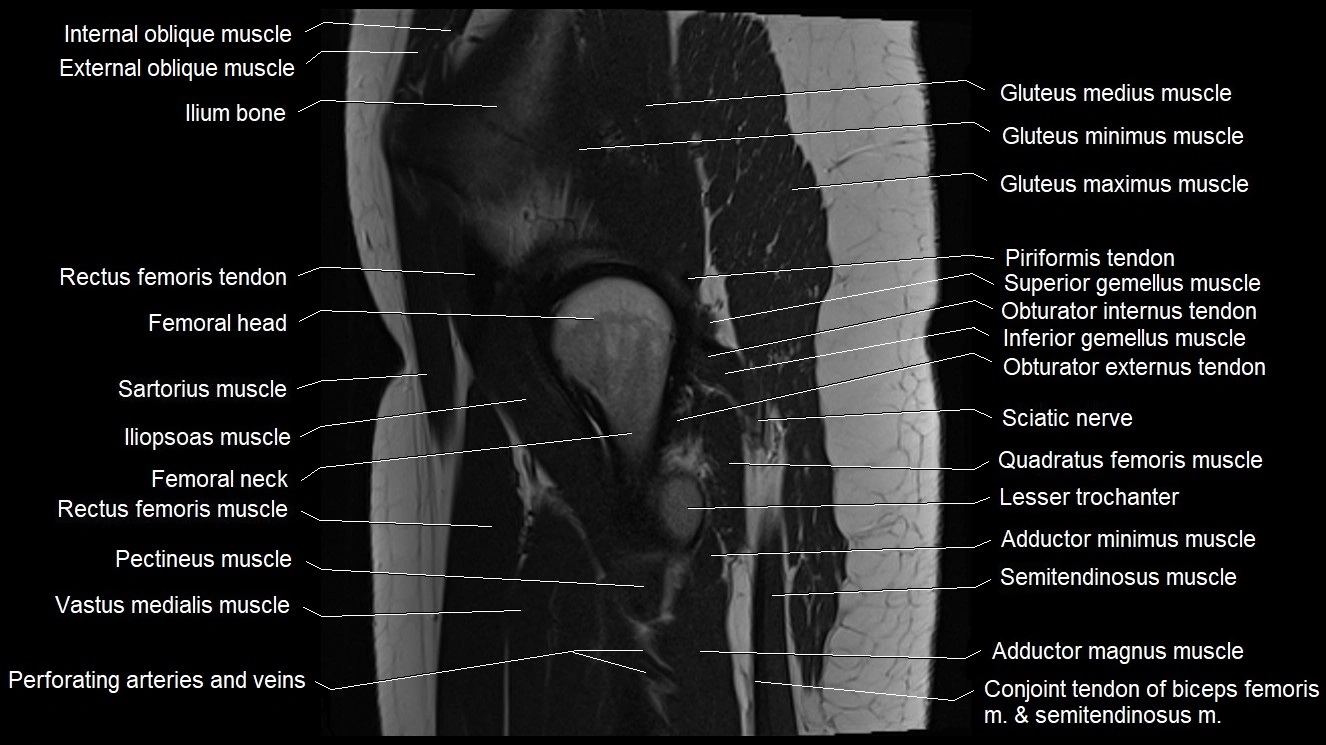

- Head of femur

- Iliopsoas muscle

- Iliopsoas tendon

- Ilium bone

- Inferior gemellus muscle

- Lesser trochanter

- Neck of femur

- Obturator internus tendon

- Pectineus muscle

- Posterior femoral cutaneous nerve

- Quadratus femoris muscle

- Rectus femoris muscle

- Rectus femoris tendon (Proximal tendon of rectus femoris)

- Sartorius muscle

- Superior gemellus muscle

- Vastus medialis muscle